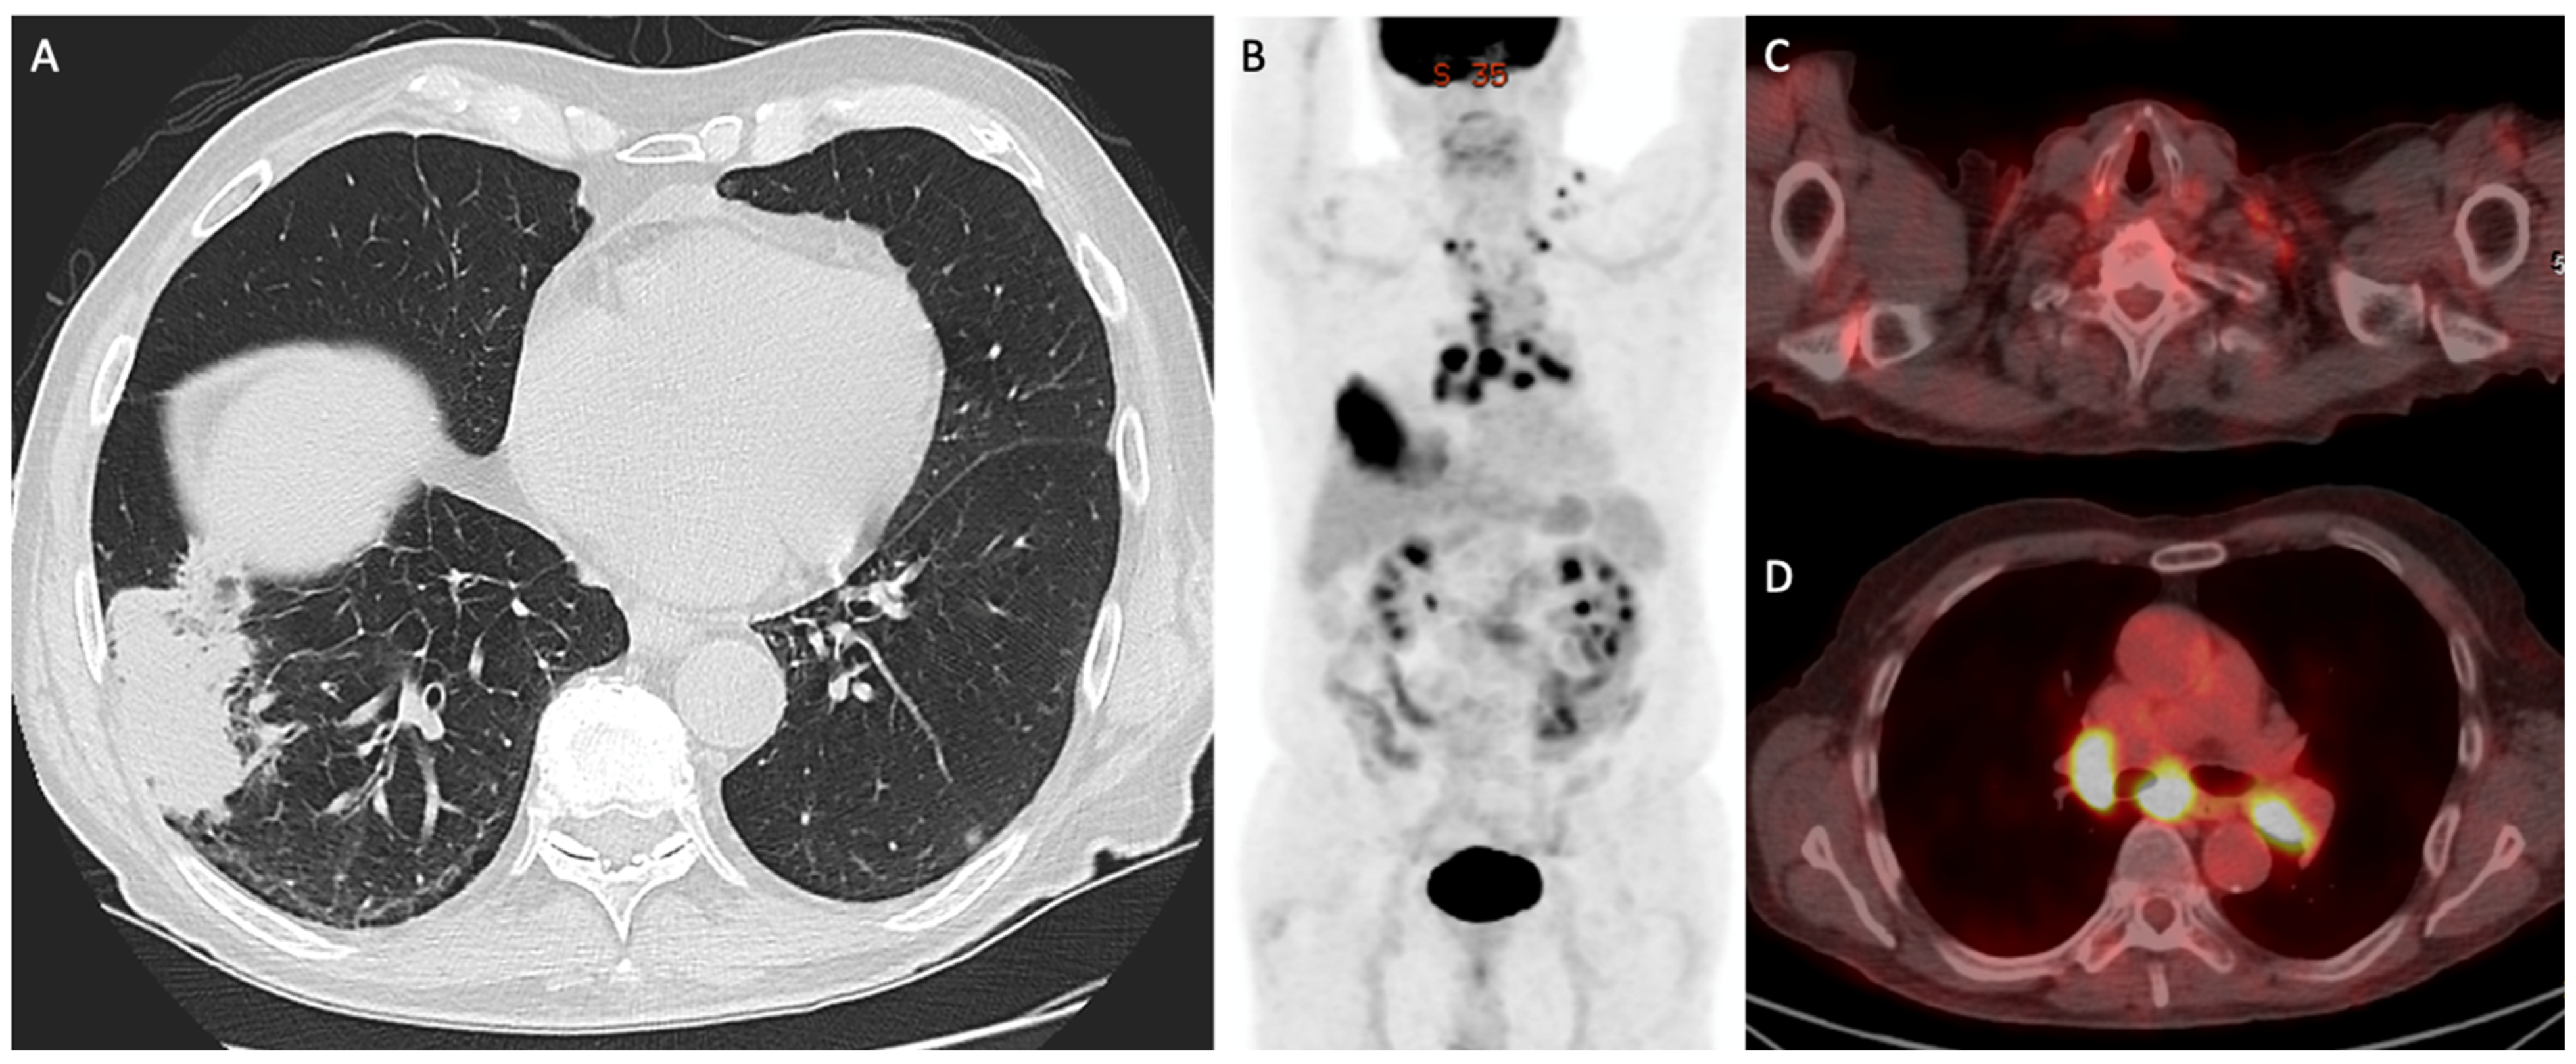

- Liu, J.; Dong, M.; Sun, X.; Li, W.; Xing, L.; Yu, J. Prognostic Value of 18F-FDG PET/CT in Surgical Non-Small Cell Lung Cancer: A Meta-Analysis. PLoS ONE 2016, 11, e0146195. [Google Scholar] [CrossRef]

- Paesmans, M.; Berghmans, T.; Dusart, M.; Garcia, C.; Hossein-Foucher, C.; Lafitte, J.J.; Mascaux, C.; Meert, A.P.; Roelandts, M.; Scherpereel, A.; et al. Primary tumor standardized uptake value measured on fluorodeoxyglucose positron emission tomography is of prognostic value for survival in non-small cell lung cancer: Update of a systematic review and meta-analysis by the European Lung Cancer Working Party for the International Association for the Study of Lung Cancer Staging Project. J. Thorac. Oncol. 2010, 5, 612–619. [Google Scholar] [CrossRef]

- Im, H.J.; Pak, K.; Cheon, G.J.; Kang, K.W.; Kim, S.J.; Kim, I.J.; Chung, J.K.; Kim, E.E.; Lee, D.S. Prognostic value of volumetric parameters of 18F-FDG PET in non-small-cell lung cancer: A meta-analysis. Eur. J. Nucl. Med. Mol. Imaging 2015, 42, 241–251. [Google Scholar] [CrossRef] [PubMed]

- Szyszko, T.A.; Yip, C.; Szlosarek, P.; Goh, V.; Cook, G.J. The role of new PET tracers for lung cancer. Lung Cancer 2016, 94, 7–14. [Google Scholar] [CrossRef] [PubMed]

- Wang, L.; Tang, G.; Hu, K.; Liu, X.; Zhou, W.; Li, H.; Huang, S.; Han, Y.; Chen, L.; Zhong, J.; et al. Comparison of 68Ga-FAPI and 18F-FDG PET/CT in the Evaluation of Advanced Lung Cancer. Radiology 2022, 303, 191–199. [Google Scholar] [CrossRef] [PubMed]

- Zhou, X.; Wang, S.; Xu, X.; Meng, X.; Zhang, H.; Zhang, A.; Song, Y.; Zhu, H.; Yang, Z.; Li, N. Higher accuracy of [68 Ga]Ga-DOTA-FAPI-04 PET/CT comparing with 2-[18F]FDG PET/CT in clinical staging of NSCLC. Eur. J. Nucl. Med. Mol. Imaging 2022, 49, 2983–2993. [Google Scholar] [CrossRef]